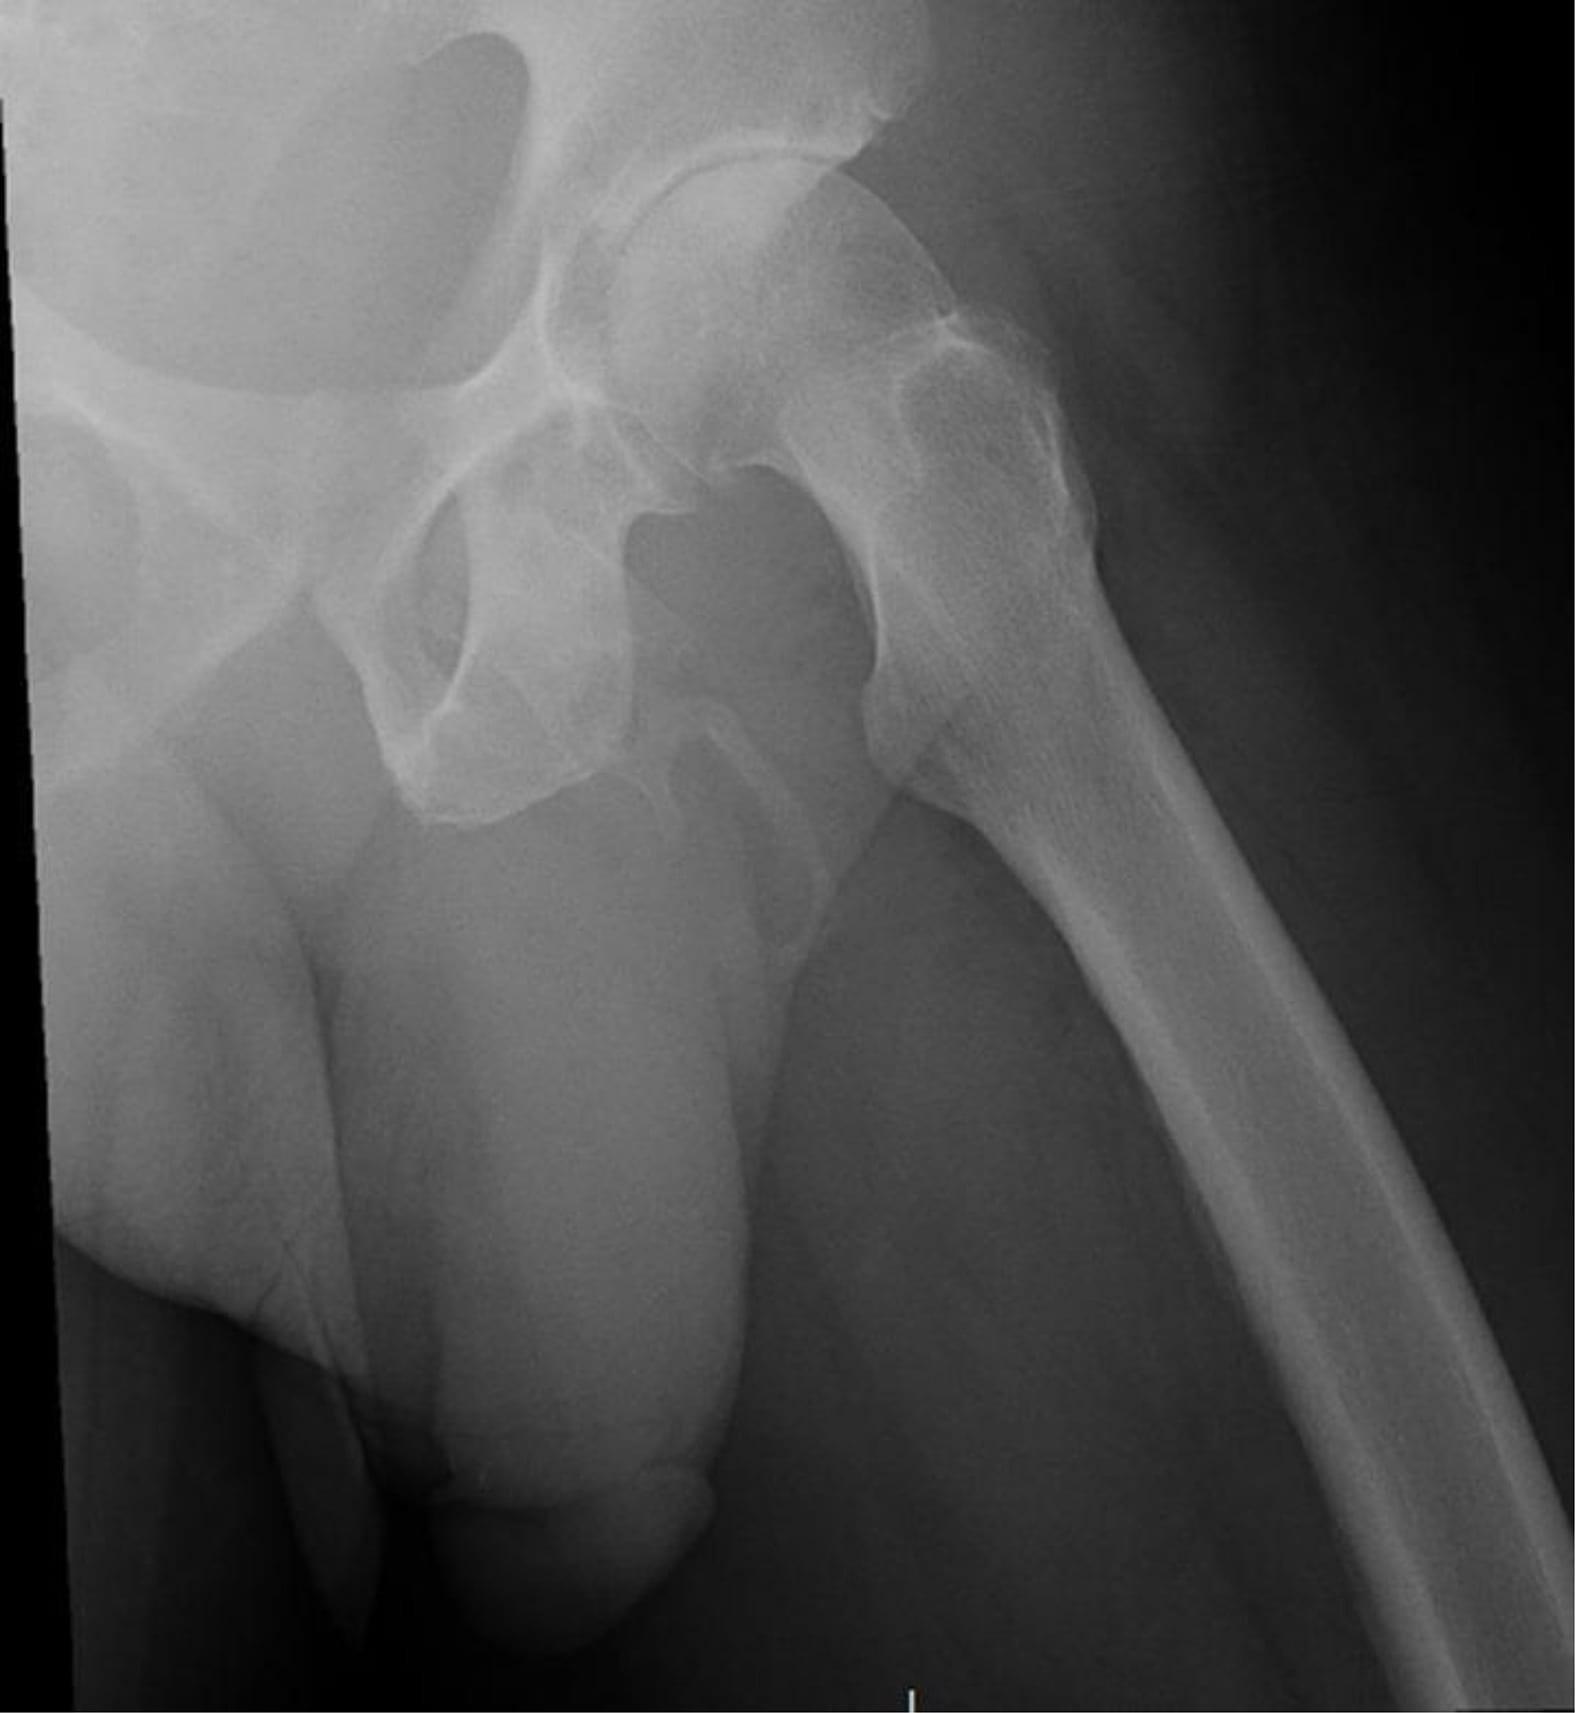

After ordering an x-ray to study the New York man’s pelvis, doctors discovered the 63-year-old’s extremely rare condition.

“An extensive, plaque-like calcification along the expected distribution of the penis was evident,” explains the report.

The Bronx doctors then realized that the man was suffering from ossification, or an abnormal formation of bone.